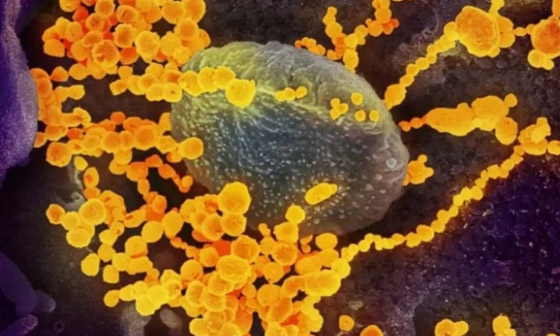

في البداية يجب أن تعلم أن العدوى الفطرية إجمالاً ليست جديدة بالرغم من تفاقم حالاتها مع ارتفاع عدد الإصابات بفيروس كورونا. وتصيب العدوى الفطرية إجمالاً الأشخاص ذوي المناعة الضعيفة، وحتى إن لم يكونوا مصابين بفيروس كورونا فهم لا يزالون عرضة للإصابة بالفطريات في حال كانوا يعانون من أمراض أخرى تؤثر بشدة على الآلية الدفاعية في أجسادهم.

وفي حين أن فيروس كورونا يؤدي إلى تفاقم مخاطر الإصابة بهذه الفطريات، لكن هناك عوامل أخرى تسبب الإصابة بالعدوى الفطرية التي تشمل الفطر الأصفر والأبيض والأسود. ويقول، ك.بوجانج شيتي رئيس مستشفى نارايانا نيترالايا التخصصي للعيون: "البكتيريا والفطريات موجودة في أجسامنا بالفعل، لكن الجهاز المناعي بالجسم يكبلها"، وأضاف: "عندما ينهار الجهاز المناعي بسبب علاجات السرطان ومرض السكري أو استخدام المنشطات، فإن هذه الأحياء الدقيقة تصبح لها اليد العليا وتتكاثر".

قبل ظهور الفطر الأصفر، عانى الكثير من مرضى فيروس كورونا من عدوى فطرية أخرى عرفت باسم "الفطر الأسود"، وتحدث الإصابة غالباً عند استنشاق الجراثيم الفطرية من الهواء. ومن الممكن أيضاً أن يؤدي مرض السكري، والتثبيط المناعي بالستيرويدات، والإقامة المطولة في وحدة العناية المركزة، والأورام الخبيثة وعلاج فوريكونازول، إلى الإصابة بالفطر الأسود.

ومثل نظيره الأصفر، يؤثر الفطر الأسود بشكل أساسي على الأشخاص الذين يتناولون أدوية لمشاكل صحية أخرى تقلل من قدرتهم على محاربة الأمراض وتضعف جهازهم المناعي. ومن أعراض المرض الألم والاحمرار حول العين و/أو الأنف، والحمى والصداع والسعال وضيق التنفس والقيء الدموي وتغير الحالة العقلية. كذلك يعاني المصاب بالفطر الأسود من التهاب الجيوب الأنفية، الألم أو الخدر أو التورم في الوجه من جانب واحد، واسوداد البشرة حول الأنف أو الحنك، وألم الأسنان، وعدم وضوح الرؤية.